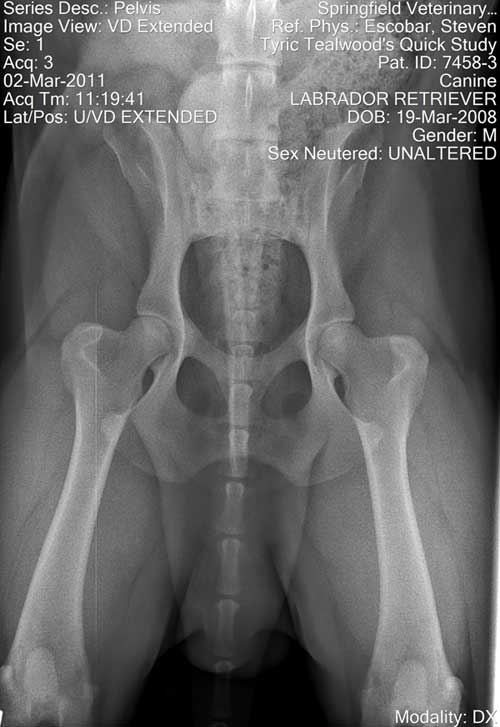

Explanation & History of Albert's OFA Hip Rating

UPDATE:  I resubmitted Albert's hips to OFA in November 2013 (at 5 1/2 years of age) and they came back rated "good".  At the same time, I did Penn Hip; that came back in the 90th percentile with a .27 and .31!  So I'm finally satisfied.

After moving to Virginia, I had my repro vet re-do Albert's hips at 35 months of age (under anesthesia).  He also looked at the picture of the 14-month prelims that I had.  His opinion was that Albert's hips were virtually identical in the 14-month and the 35-month x-rays ... there had been NO changes.  He felt that we had a strong good, possibility of an excellent.

These last x-rays came back from OFA rated "

fair".  I talked with Dr. Keller, who was very open.  He said he had seen the x-rays as soon as they came in, and that  "they should at least be a good".  Before I could challenge him further, he explained that the other two orthopedic specialists had access to the previous rating and "probably were afraid to take too big a jump" from the previous "borderline" rating.

I may re-do Albert's hips but, at present, cannot afford to pay for a fourth attempt.  So, I'm offering this explanation and a pretty good picture of Albert's most recent hip x-ray, taken at 35 months of age.  Although I fully realize that a "fair" IS a pass on hips, in this case it is not a correct representation.